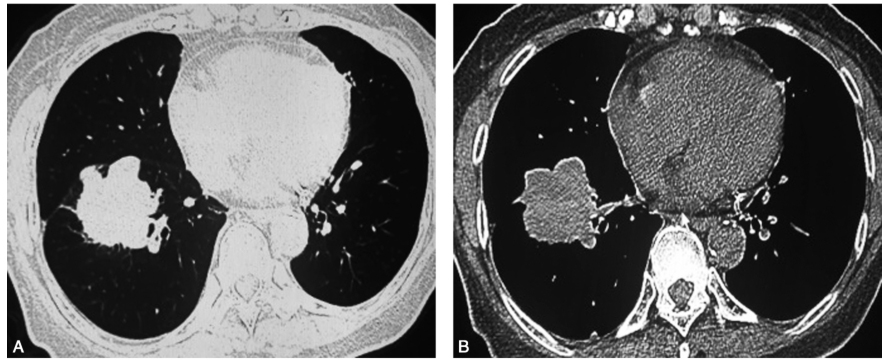

患者女性,77岁,主因“咳嗽,痰中带血5天”入院。患者于2018年1月1日无明显诱因间断出现咳嗽,痰中带鲜血,量不多,无胸闷、气喘,无胸痛、气急,无发热、盗汗和体重下降,于当地医院查血肿瘤标志物CEA增高。外院胸部CT扫描示右肺下叶可见大小约4.3 cm×4.1 cm的不规则软组织影,边缘毛糙,可见毛刺,分叶及胸膜凹陷征;右肺门淋巴结肿大,隆突下淋巴结增大(图1)。骨扫描示左前第3、6肋骨局限性浓聚。头颅MRI未见明显异常。腹部与浅表淋巴结超声检查未见明显异常。为进一步诊治入我科。患病以来精神好,胃纳可,睡眠好,大小便正常,无体重明显下降。

图1外院胸部CT扫描(2018-01-01)示右肺下叶大小约4.3cm×4.1cm的不规则软组织肿块影,边缘毛糙,可见毛刺征及分叶征

A.肺窗;B.纵隔窗